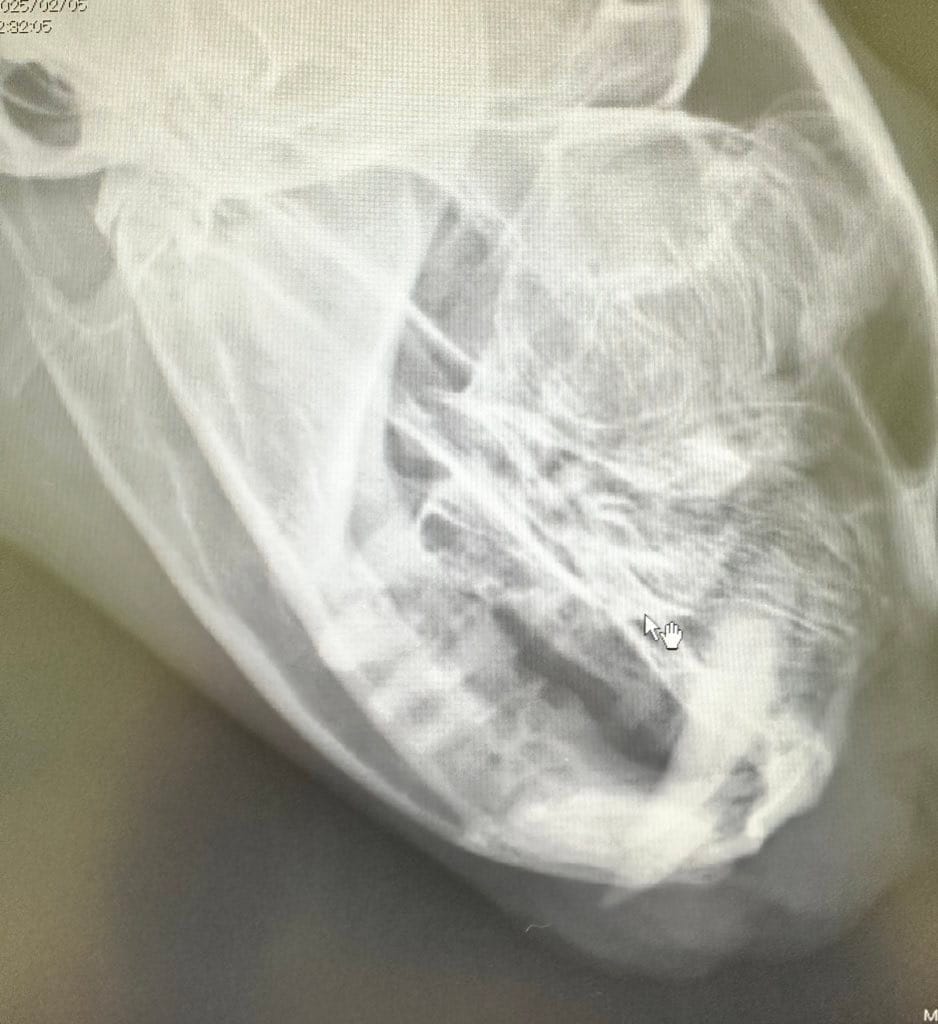

抜いた臼歯です。猫の臼歯は14本ですが、ドリルで分割して抜歯をするため数が多く見えます。